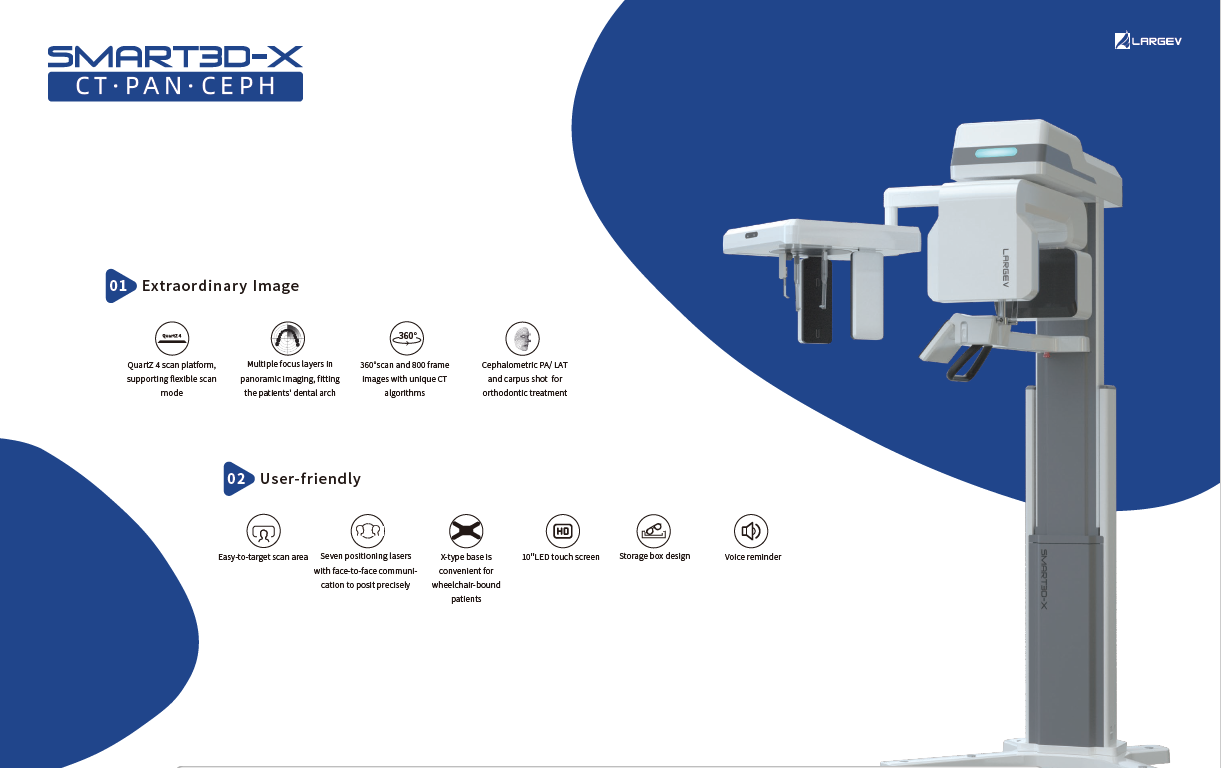

Dental CBCT by LargeV – AI-Enhanced 3D Imaging and Panoramic X-Ray

To begin with, the Dental CBCT by LargeV delivers advanced AI-powered 3D imaging and panoramic X-ray designed for accurate dental diagnostics and treatment planning.

It ensures detailed visualization of oral structures while keeping radiation exposure low and image quality high.

Moreover, this system combines precision and efficiency, helping clinicians diagnose faster and treat patients with greater confidence.

CT / CEPH / PAN Dental CBCT Functions

The LargeV CBCT supports CT, CEPH, and panoramic imaging in one compact system.

Three Scan Modes of Dental CBCT Imaging System

Additionally, the system provides three flexible scan modes to match clinical needs. Multiple focus layers in panoramic imaging fit each patient’s dental arch perfectly.

360°scan and 800 frame images with unique CT algorithms

360°scan and 800 frame images with unique CT algorithms -

QuartZ 4 scan platform, supporting flexible scan mode

QuartZ 4 scan platform, supporting flexible scan mode -

Multiple focus layers in panoramic imaging, fitting the patient’s dental arch

Multiple focus layers in panoramic imaging, fitting the patient’s dental arch -

Easy-to-target scan area

Easy-to-target scan area -

Six positioning lasers with face-to-face communication to posit precisely

Six positioning lasers with face-to-face communication to posit precisely -

X-type base is convenient for wheelchair-bound patients

X-type base is convenient for wheelchair-bound patients -

10"LED touch screen

10"LED touch screen -

Storage box design

Storage box design -

Voice reminder

Voice reminder

Product Size Display of LargeV Dental CBCT Machine

Designed for space efficiency and comfort. Every detail supports easy operation and clear imaging results.